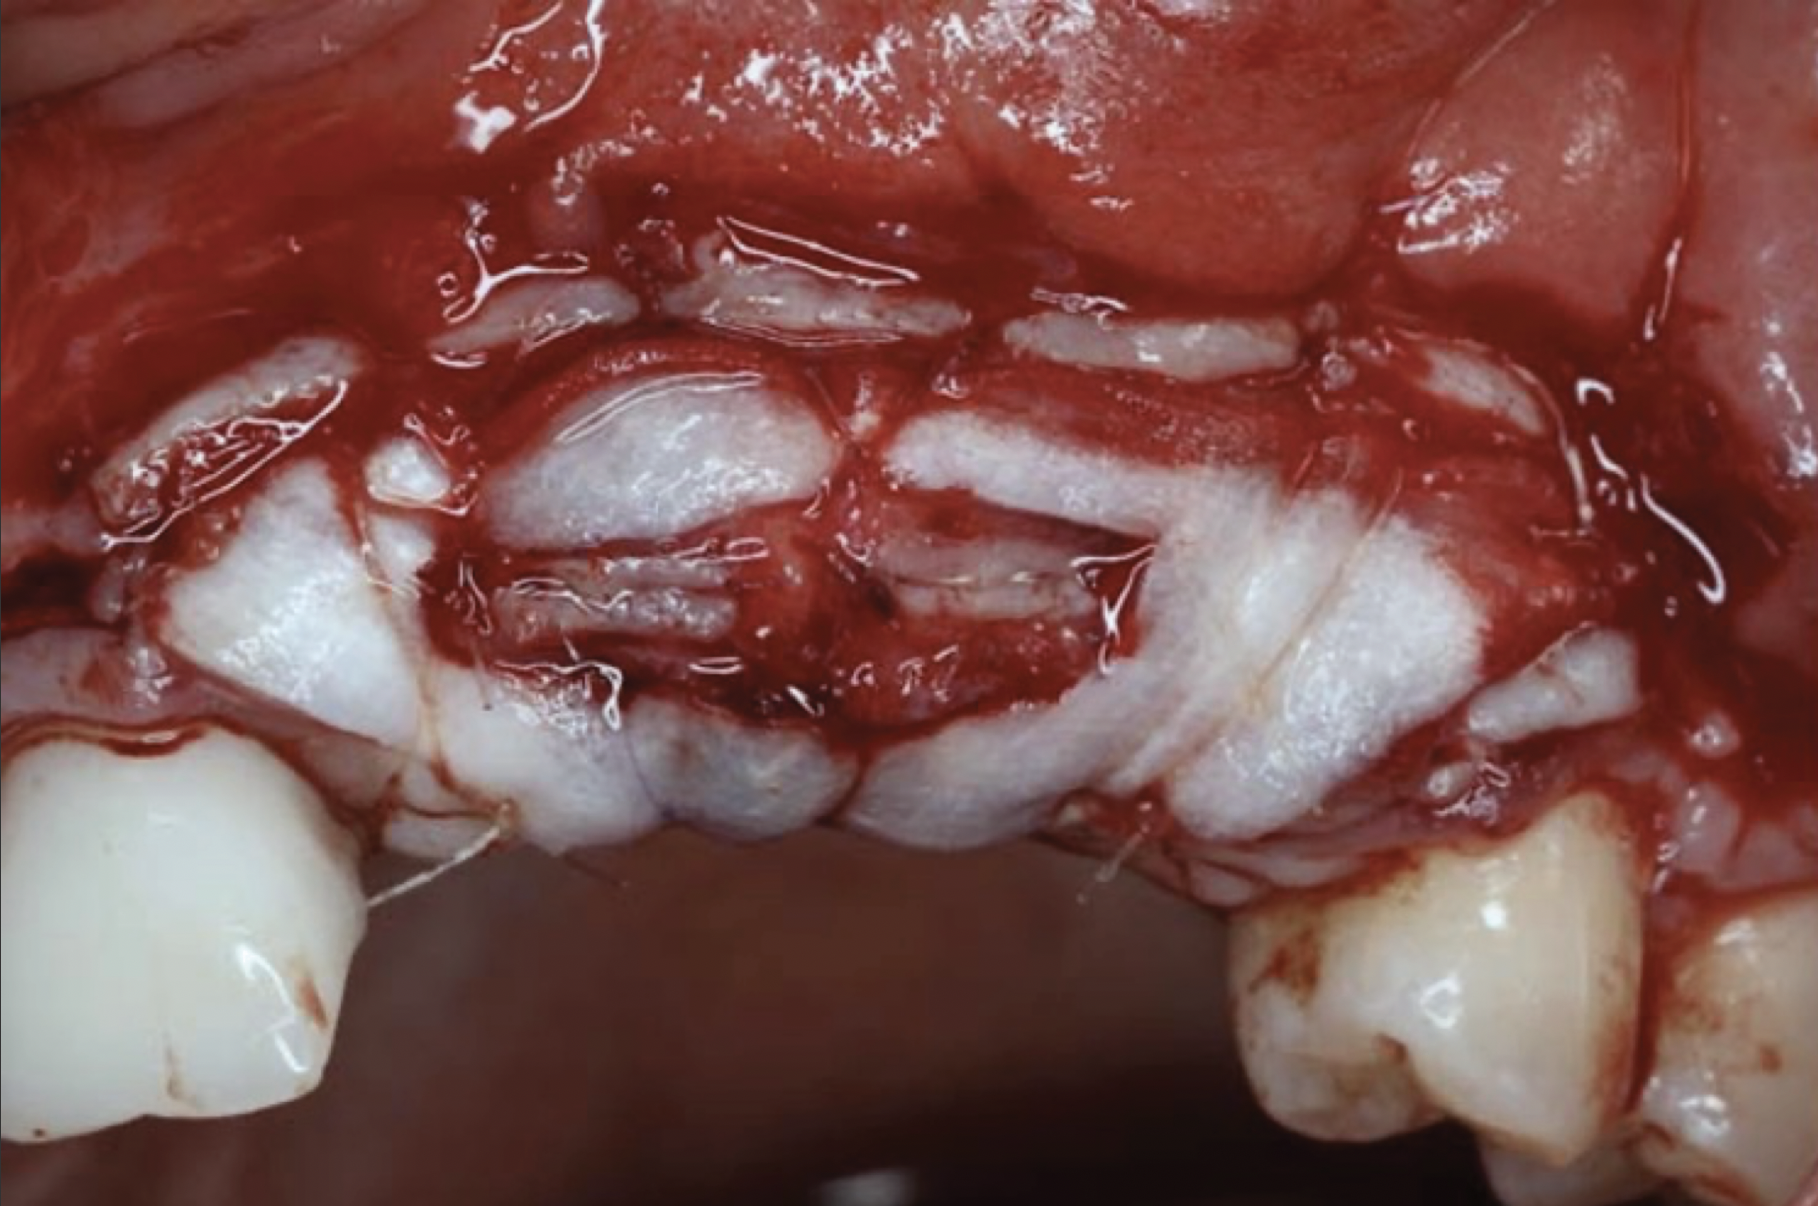

To enhance the esthetic outcome of the implant therapy, a split-thickness flap was opened at the level of the occlusal and buccal aspects of the implants. Two connective tissue grafts (CTGs) were harvested from the palate and sutured over the implants (Figure 11). Two additional CTGs were also obtained and positioned between the implants to augment the peri-implant papillae. This augmentation technique has been described as the "iceberg" connective tissue graft (iCTG) approach (Figure 12).16 The flap was released and sutured to completely cover the CTGs.

Fig 11. Soft-tissue augmentation with two CTGs.

Figure 11

Fig 12. Two additional CTGs were placed between the implants (ie, the “iceberg” CTG approach).

Figure 12